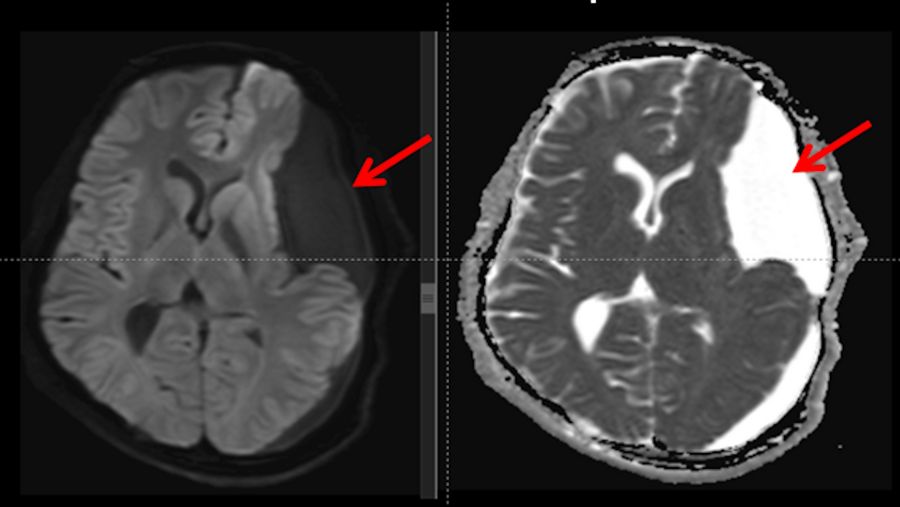

Diffusion and ADC (Apparent Diffusion Coefficient) MRI brain sequences

The brain MRI in the diffusion and ADC map sequences revealed no diffusion restriction of the cyst, confirming the preoperative hypothesis of a large arachnoid cyst (represented by red arrows), excluding the possibility of dermoid and epidermoid cysts.

Fig. 4: Diffusion and ADC map sequences show a large arachnoid cyst with no diffusion restriction, excluding the possibility of a dermoid and epidermoid cysts, as well as that of an empyema and an abscess.